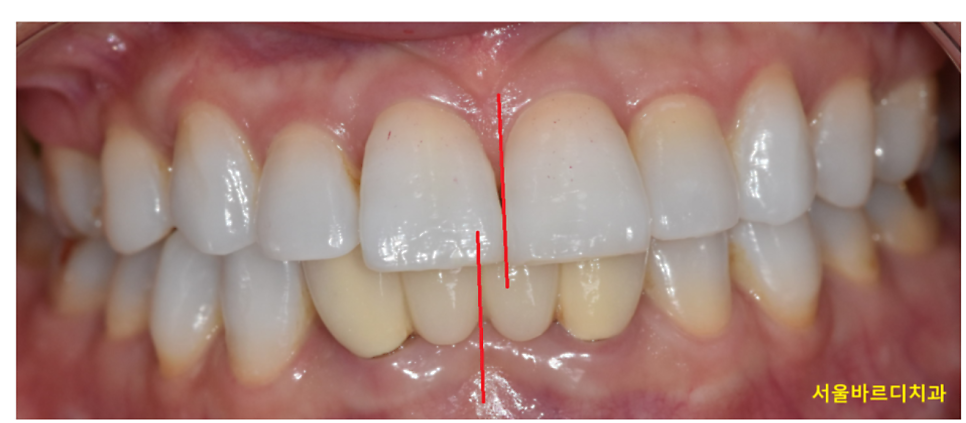

치아의 중심선이란,

위 앞니 두 개의 중앙과 아래 앞니 두 개의 중앙이 일직선상에 있는지를 의미합니다.

이상적인 교합에서는 이 중심선이

코 가운데와 일치하는 것이 가장 이상적이지만,

250328 정중선이 안맞는 경우

사람 얼굴이 비대칭일 수도 있고

치아가 결손됐을 수도 있고

여러 원인으로 중심선이 1-2mm 정도 어긋나서

치료가 마무리 될 수 있는데요.

중심선이 어긋나있다고 반드시 교정이 잘못됐다고 단정할 수는 없습니다.

250214 중심선보다 중요한건 교합이에요!

실제로 대부분의 사람들이 웃거나 말할 때

중심선의 미세한 어긋남을 인지하지 못하며,

본인이 신경 쓰지 않으면 주변 사람들은 전혀 알아채지 못합니다.

(정말 많이 틀어져있지 않는 이상요!)